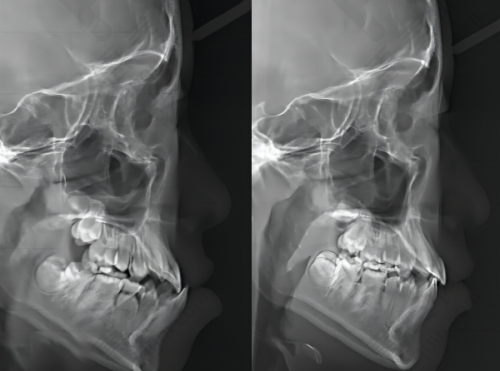

牙齿矫正项目也特别出色,能做全同步带状弓矫正、时代天使隐形矫正、儿牙时代天使早期矫正等项目,大人小孩都可以同时来进行矫正。除此之外,还有全瓷牙冠、牙齿瓷贴面、洗牙、补牙、儿童牙齿涂氟、牙周护理(超声洁牙 + 抛光套餐98元,清除茶渍烟渍)、残根接续、烤瓷牙、根管治疗、牙齿美白、地包天治疗、活动义齿等其他项目。

刘昊擅长对局部、全口牙功能性美观修复,口腔科常见疾病治疗,中老年全口修复,吸附性功能义齿,全口美观修复等专精项目。李红艳现任力军美合口腔医疗主事,曾分别在内蒙古民族大学附属医院和吉林大学第二口腔医院进修,擅长口腔正畸、种植牙、牙列畸形、牙齿不齐等。孔祥华在北京305医院、北京三院进修学习,擅长于牙周病、牙体牙髓病治疗,中老年全口修复、吸附性功能义齿等项目,以及儿童口腔病治疗预防和保健。